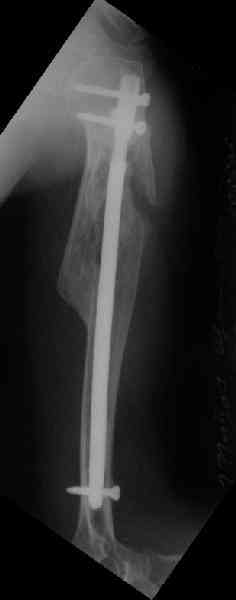

Здесь нет необходимости в серкляже. Вмешиваться на промежуточных отломках приходится, если есть угроза перфорации кожи, или промежуточный отломок попал в фасцию, как пуговица в петлю. В приложении сегментарный оскольчатый перелом плеча в проксимальном отделе, фиксированный больщеберцовым стержнем. Как видите, обошлось без серкляжа. Функция полная.